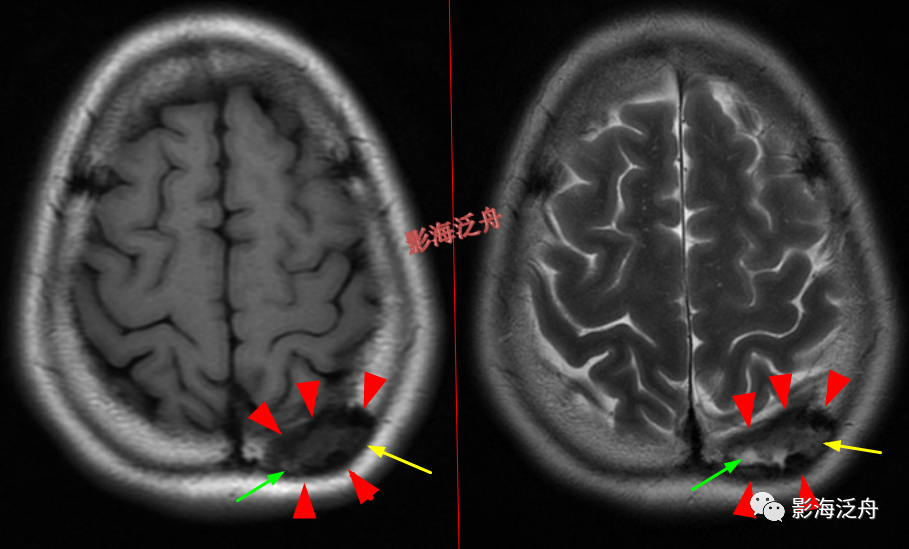

脑膜炎

患者,桥前池内可见异常增多的血管影(红箭),正常人的桥前池因为脑脊液流动产生的伪影也可以看到池内絮状低信号(绿箭),但不如右侧患者的明显,这个观察起来比较困难,就如在腹部CT

上观察患者是否存在肝脏肿大一样,需要一个经验积累的过程。黄

箭指基底动脉,蓝箭指三叉神经。